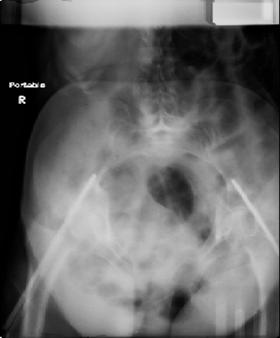

attached are images of a 70 year old female after peds versus car. her own car ran her over.

injuries are limited to the pelvis. left rami open and visible in a 10cm vertical laceration just lateral to left labia majora. wound is grossly clean. no vaginal and no urinary issues. CT scan shows widening of both SI joints anteriorly but I think this is vertically stable pattern.

pt treated that night with I/D and supra-acetabular frame to close the ring. consideration was given for SI screws bilateraly, but given time of night and other factors decision made not to proceed.

so the question is what next operatively if anything? concerns are infection, nonunion anteriorly and possible incompetence of the pelvic floor which may lead to prolapse issues. right rami are comminuted and plating may entail ilioinguinal approach to extend plate laterally to right iliac wing. retrograde screw up right rami is an option but I am not convinced it will add much. adding SI screws very doable, but major concern is restoring anterior ring. so far wound is clean and closed over a drain, and I have no plans to open it back up and wash again.

maintaining pelvic alignment in ex-fix in 70 yo female for any length of time may be challenging.

any thoughts? would anyone plate the pubic symphysis to close the gap and leave the more lateral rami fractures alone? the most recent pelvic case on this website involved pts with suprapubic catheters and antibiotic options including resorbable beads. I wonder how many people would plate and place antibiotic beads. thanks.

Отправитель: dan schlatterer 12 Июнь 2007, 04:47

attached are several CT cuts. please let me know if you need more. the CT is pre-pelvic ex-fix placement.

Thank you.